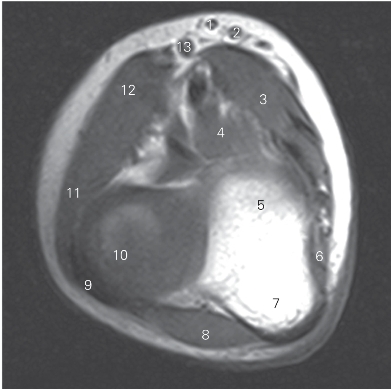

图4-33 经肘关节下份的横断层MR T1加权图像

1 头静脉 cephalic vein 2 贵要静脉 basilic vein

3 旋前圆肌 pronator teres 4 肱肌 brachialis

5 肱骨滑车 trochlea of humerus

6 指深屈肌 flexor digitorum profundus

7 尺骨鹰嘴 ulnar olecranon 8 肘肌 anconeus

9 桡骨环状韧带 annular ligament of radius

10 桡骨头 head of radius

11 桡侧腕长、短伸肌 extensor carpi radialis longus and brevis

12 肱桡肌 brachioradialis 13 肱静脉 brachial vein